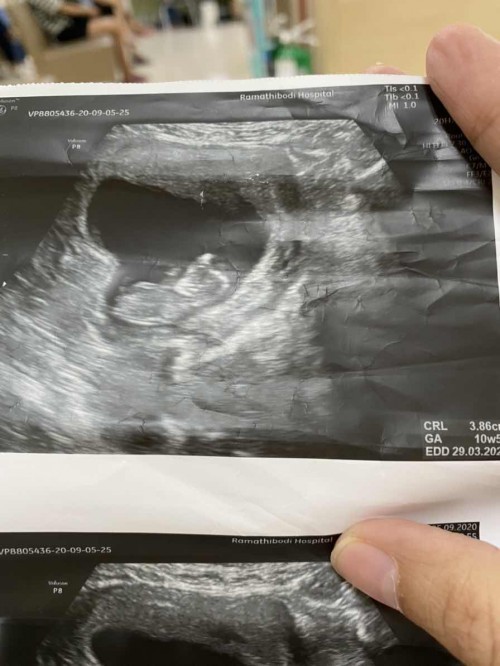

รูปที่ซาวด์ตอน10w5d ค่ะ

ตอนนี้ 13 week จ้า